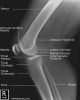

3. Lateral Knee View

Demonstrates: femorotibial articulation, patellofemoral articulation, Femoral condyles should be superimposed.

Helpful for: Knee Arthritis, Tibial Plateau Fracture, Distal Femur Fracture, Patellar Fracture, Patellofemoral Arthritis

Position: lateral with affected side down and flexed 30° at the knee. The contralateral leg is shifted posteriorly out of the way.

Beam directed at knee joint with 5° cephalad angulation.